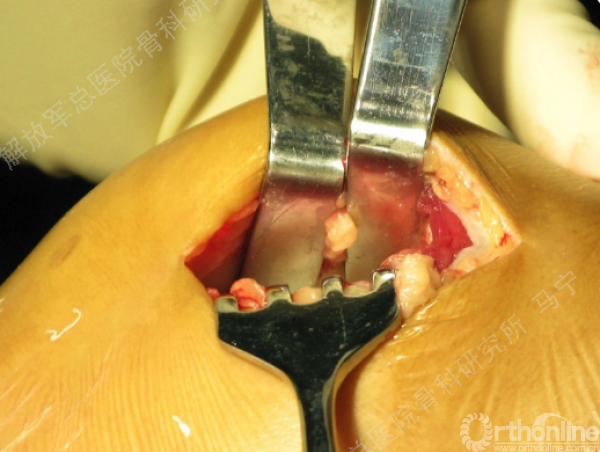

手术切口:根据软骨损伤部位来确定手术切口入路。

术中所见和影像检查一致。

软骨损伤区的清创。